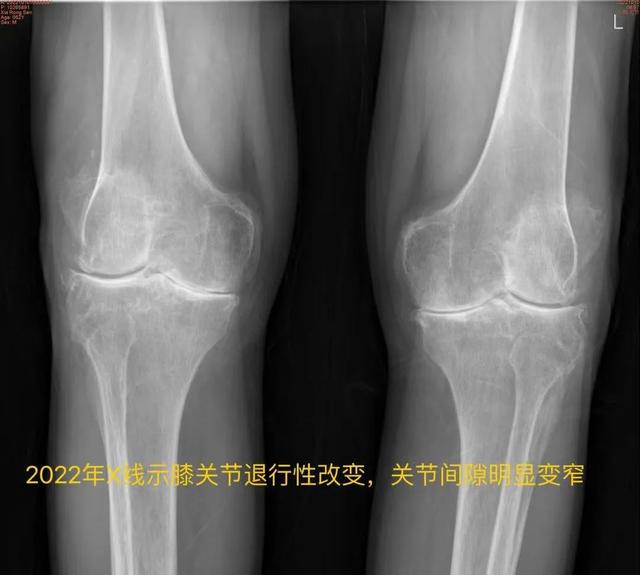

今年64岁的王大爷(化姓),双侧髋、膝关节疼痛十余年,六年前因“腰腿疼痛”于上海长征医院行腰后路减压植骨融合内固定术,同年于上海新华医院内分泌/遗传科行基因检测诊断为“黑尿病”,四年前因“左髋疼痛”于我院行“左侧人工全髋关节置换术”,一年前因“右膝疼痛”于我院行“右侧人工全膝关节置换术”。

近日,王大爷因“左膝关节步行活动后疼痛加剧”门诊拟“黑尿病性膝关节炎”再次入住我院骨科,入院后查体:全身皮肤出现黑色素沉着,以面部及耳廓皮肤黑色斑块沉着明显,左膝关节周围肿胀,有压痛,左膝关节屈曲100°,伸直约10°(正常膝关节活动度为屈曲135°,伸直0°)。

骨科主任 徐宏扣

关节疾病是黑尿病病情发展的最终结果,也是疾病致残的主要原因。随着病情的发展,它会累及关节软骨以及重大关节和大脊椎,所以黑尿病患者不可避免地会有慢性退行性关节病。也正是因为如此,该病在临床中极易引起误诊、误治!